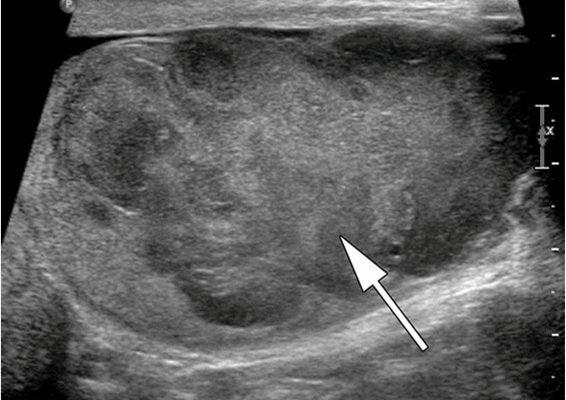

Ультразвуковое исследование (УЗИ) мошонки является предпочтительным начальным визуализирующим исследованием для оценки образования яичка. УЗИ может подтвердить наличие новообразования, определить его расположение и оценить состояние противоположного яичка (рис. 4). Чувствительность метода достаточно высокая - от 92 % до 98 %.

Снимок УЗИ яичка

При любом изменении эхоструктуры яичка врачи сонологи прежде всего исключают злокачественную опухоль. Первоначально новообразование преимущественно локализуется по задней части яичка. В течение длительного времени объём и форма мужской половой железы могут не изменяться. В большинстве случаев опухоль является гипоэхогенной с мелкими беспорядочными внутренними эхосигналами (лимфома, семинома), но возможны гиперэхогенные (эмбриональная карцинома, тератомы, хорионэпителиома) и смешанные структуры.